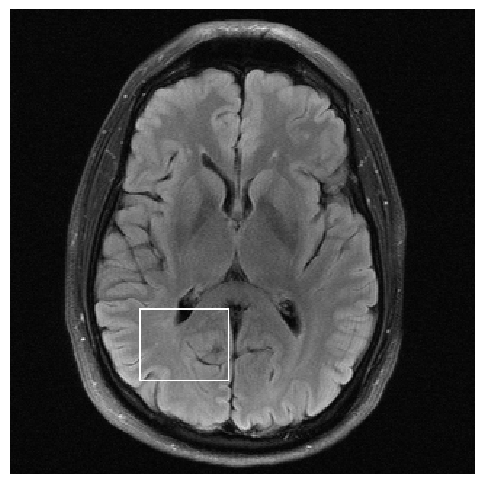

Figure 3: Reconstructions results. Rows 1 and 3: Examples of comparing the ground truth (GT) fully sampled image to the reconstructed images obtained by the three models (1-3), NPB-REC, baseline, E2E-VarNet trained with Dropout, and the NPB-REC std. map at accelerations R=4𝑅4R=4, R=8𝑅8R=8, respectively. Rows 2 and 4: The corresponding annotated ROIS of Nonspecific white matter lesions.

Fig. 3 presents examples of reconstruction results obtained by (1) our NPB-REC approach, (2) the baseline, and (3) Monte Carlo Dropout, for equispaced masks with two different acceleration rates R=4𝑅4R=4 and R=8𝑅8R=8. The reconstructed images predicted by the three models are smoother than the reference image. This is due to the fact that all the models were trained with SSIM loss, which tends to produce overly smooth reconstructions while preserving the diagnostic content and the anatomical features Sriram et al. (2020a). These images can be enhanced by dithering the image by adding a small amount of random Gaussian noise to produce a more textured reconstruction, as proposed in Sriram et al. (2020b).

Table 1 presents the mean PSNR and SSIM metrics, calculated over the whole inference set, for the three models. Our NPB-REC approach achieved significant improvements over the other methods in terms of PSNR and SSIM (Wilcoxon signed-rank test, pmuch-less-than\ll1e-4, except for SSIM values in line W, R=4𝑅4R=4 where they are roughly the same for NPB-REC and Baseline). The improvement in the reconstruction performance can be noted both quantitatively from the metrics, especially for masks with acceleration rate R=8𝑅8R=8, and qualitatively via the images of annotations, where our results show less smoothness than those obtained by Dropout.